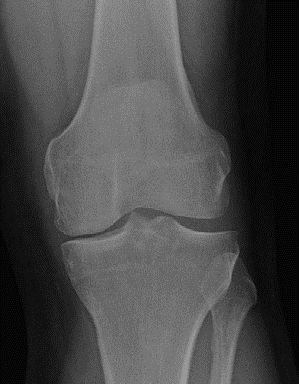

KNEE Structured oralexamination question4: Unicondylar knee arthroplasty ( UKA ) versus high tibial osteotomy…

KNEE Structured oralexamination question5: Unicondylar knee arthroplasty (UKA) versus total knee replacement …